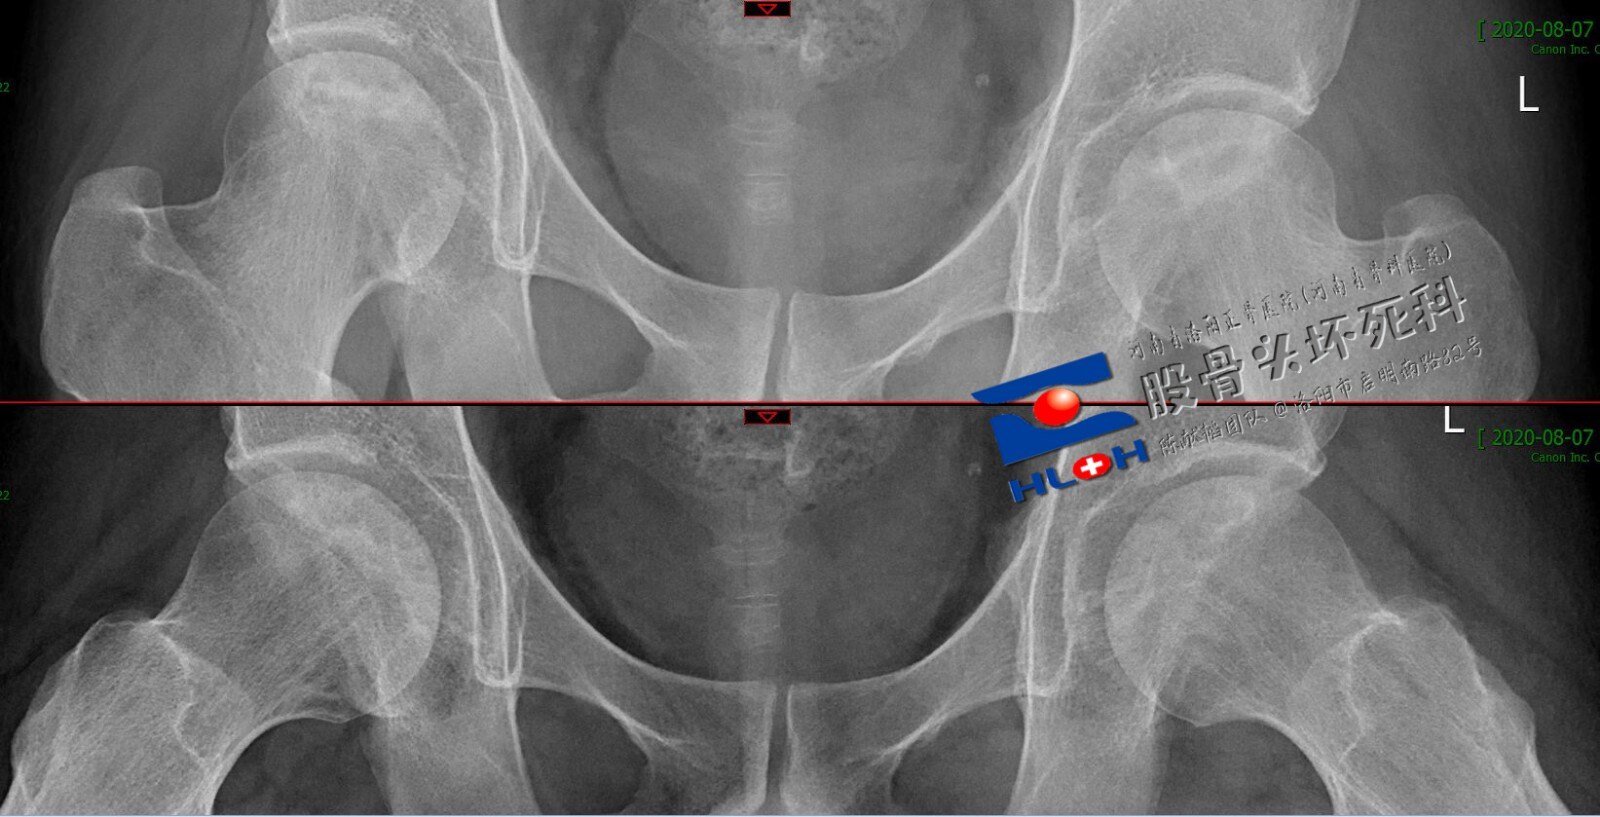

图2-6-1Ⅰ型-Ⅳ型股骨头脱位的x片表现.jpg

荐髂关节脱位,股骨头脱位